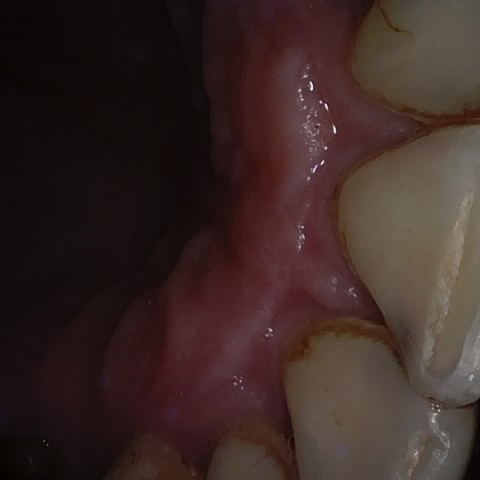

Annotated as "Good"